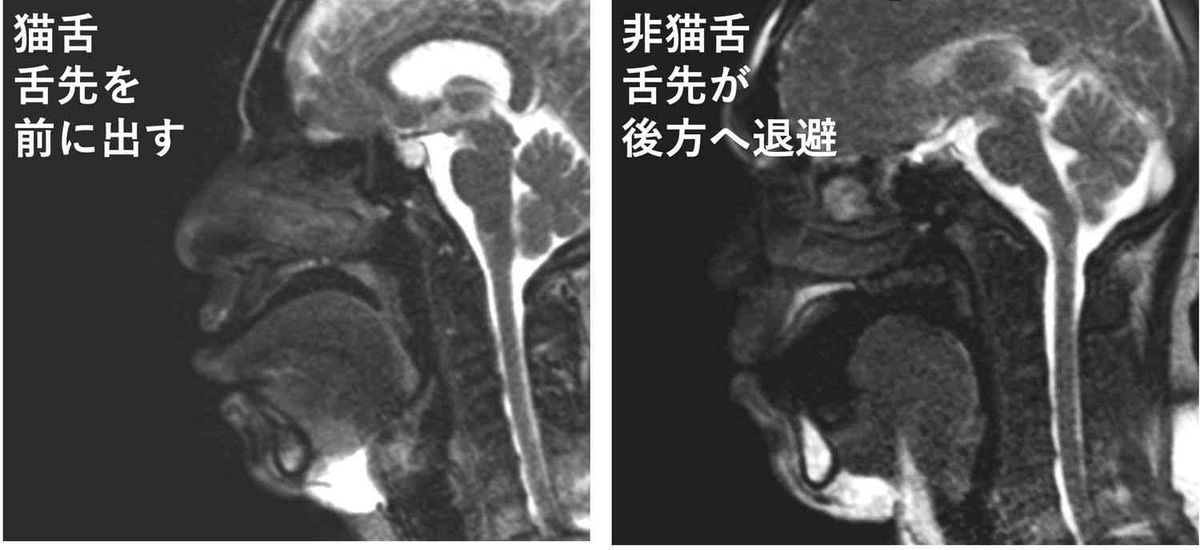

下の画像の左側が“猫舌群”、右が“非猫舌群”だ。 猫舌ではない人の場合、お茶が口に入ると舌が後方に移動して、下の歯と舌の間に“ポケット”を作り、そこにお茶を溜めている。そのあとで舌の周囲を伝ってのどへと流し込んでいくのだ。 一方の猫舌の人は、まず最初に舌先をお茶に接することからスタートする。非猫舌群の人が終始舌先をお茶に接しないようにしているのとは正反対の動きだ。 熱いものを食べる時には意識的に舌は奥へと引っ込め、舌の下のポケットに一旦収めるようにトレーニングすればいいのだ。熱いものが食べられない……「猫舌」を徹底的に研究してわかった“そうでない人”の決定的な違い | 文春オンライン